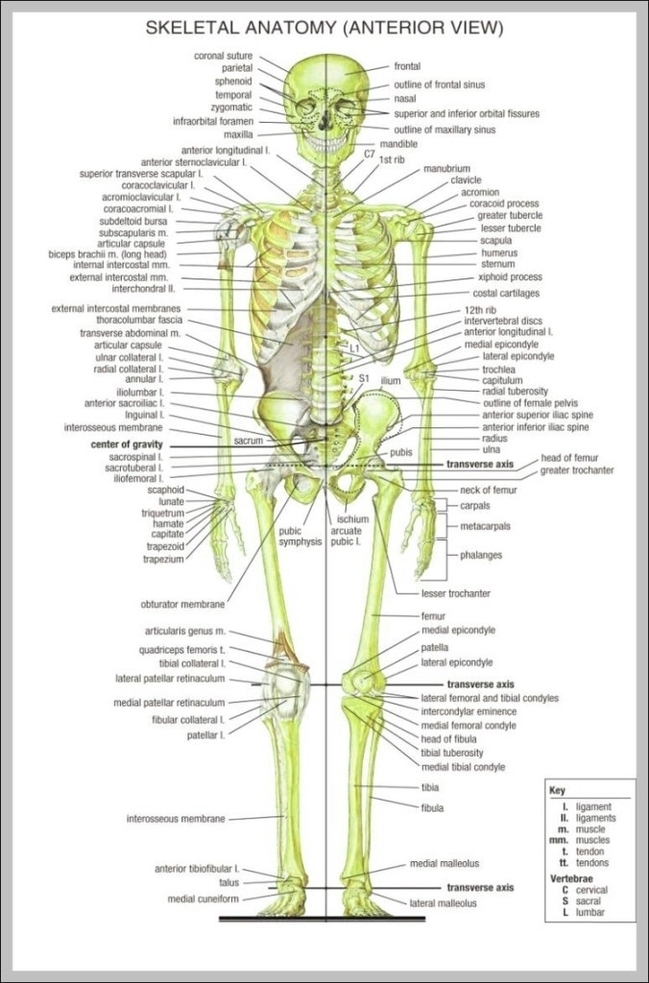

Cellular Components of Bone Diagram

The Cellular Components of Bone diagram zooms to the microscopic level with osteoblasts building matrix, osteocytes living inside lacunae, osteoclasts breaking bone down, and the osteon units with their central…